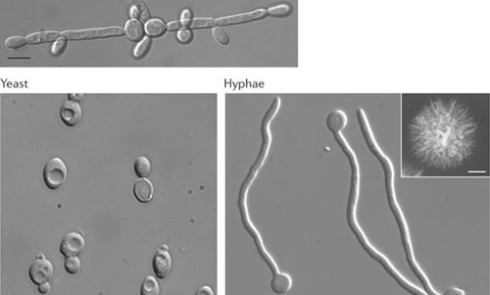

À la naissanceLe nouveau-né possède une cavité buccale aseptique indemne de toute présence bactérienne, fongique et sans aucune défense immunitaire....Prise en charge palliative d’un carcinome épidermoïde de la pyramide nasale : à propos d’un cas